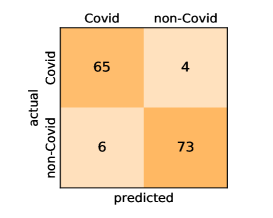

Our models achieve fairly good performance compared with the recently published work using the exact network architectures. This can bet attributed to a better optimization of our models and the effectiveness of our fine-tuning strategy using custom-sized inputs determined specifically for each architecture. Here, we see that DenseNet201 outperforms all other architectures. The model achieves average accuracy and sensitivity scores of and , respectively. It also identifies all COVID-19 images with only four images, on the average, are falsely predicted as Non-COVID-19. DenseNet169 achieves the second best average accuracy of and a very high sensitivity identical to the best model. The DenseNet121 and Xception models have nearly identical results for all evaluation metrics. We observe that small-sized networks such as ResNet18 achieves comparable results with other deeper models. The SqueezeNet and ShuffleNet models perform at a similar level of accuracy. The variants of the ResNeXt models have comparable results and perform as good as the different ResNet variants. A detailed analysis on the class-wise results for individual models is presented in the confusion matrices in Figure 10.